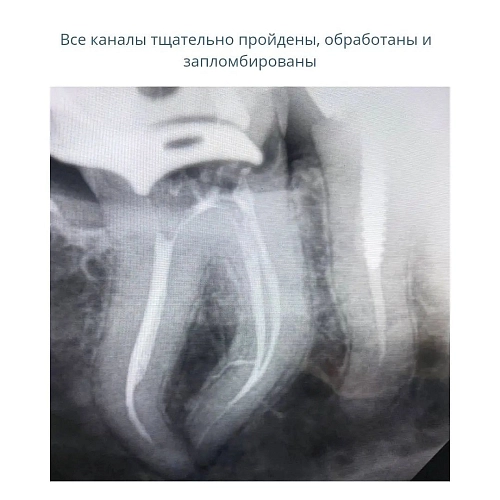

На снимке лечение сложного зуба мудрости со склерозированными каналами.

Лечение проводила врач - стоматолог - микроскопист Гордеева Людмила Валерьевна.